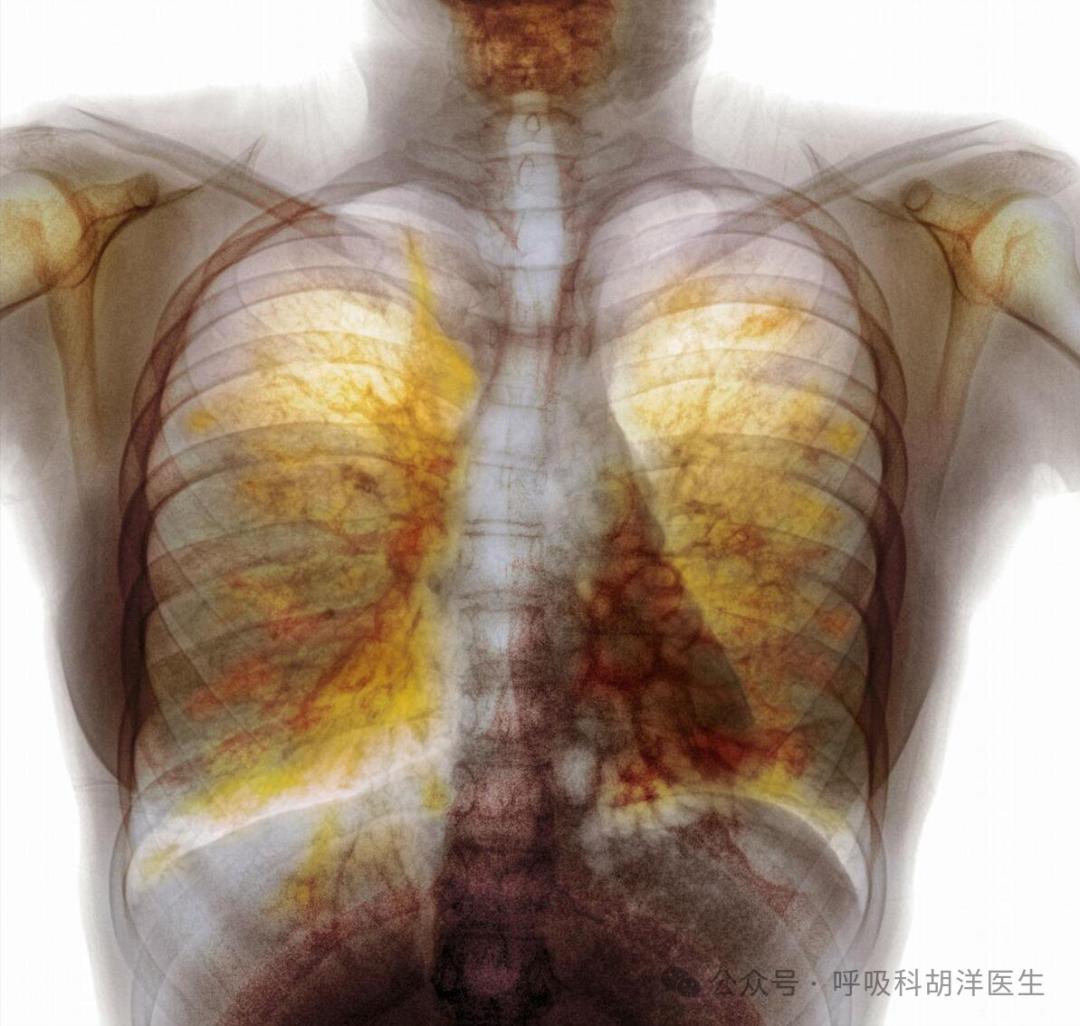

“目前CT还没有发现占位性病变。”话音未落,患者如释重负地松了一口气。然后我调出了双肺底部的网格阴影:“但是有间质变化,需要调查特发性肺纤维化。”患者听到这个消息后惊呆了,承认最近有渐进性呼吸不畅。虽然建议住院健全肺功能,高分辨率CT和病理检查,但患者以“不是癌症”为由拒绝了,最后带着药离开了医院。

注意:特发性肺纤维化(IPF)五年生存率甚至低于部分恶性肿瘤,是间质性肺疾病中最危险的亚型。其特征性病理改变为普通间质性肺炎(UIP),目前,除吡非尼酮、尼达尼布等抗纤维化药物可以减缓病程外,肺移植仍然是终末期患者唯一有效的治疗方法。这个病例警告我们,面对杵状指体征时,除了排查肺癌外,还要对间质性肺病等系统性疾病保持警惕。